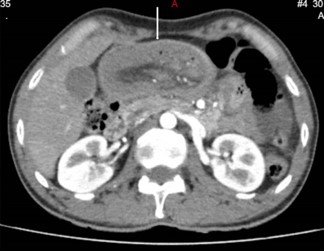

A 48-year-old otherwise healthy male presented to national hospital of Sri Lanka in September 2024 with a complaint of intermittent left iliac fossa pain for 6 months duration. The pain was colicky in nature which lasts for about 10 minutes. This was associated with loss of appetite and loss of weight of 6kg over a period of 4 months. He also complained of constipation predominant altered bowel habits for the same duration. He has never had per rectal bleeding. During this period the patient has had multiple hospital admissions in which he has been managed with the suspicion of diverticular disease and ureteric colic. However, he has never had episodes of intestinal obstruction. He has never had previous abdominal surgeries as well. During these admissions he has been evaluated with upper and lower gastrointestinal endoscopy and ultrasound scan of the abdomen which did not show any remarkable finding. In this admission he complained of similar type of abdominal pain with bilious vomiting and absolute constipation for 4 days duration. On examination he had a soft distended abdomen with an empty rectum in the digital rectal examination. He was neither febrile nor tachycardic. The blood investigations were unremarkable. It was decided to proceed with contrast enhanced CT of the abdomen which showed evidence of telescoping of the jejunal loops with the lead point in the mid jejunum (Figure 1). CT abdomen further showed a submucosal fat density in mid jejunum which is likely to be an intestinal lipoma which could be the lead point. Since the patient has been having recurrent episodes and considering the chance of adult intussusception having a lead point which will predispose the patient for future intussusception, it was decided to proceed with diagnostic laparoscopy with or without laparotomy. The diagnostic laparoscopy revealed a dilated proximal jejunal loop with thickened bowel wall. No lead point was noted macroscopically. As the laparoscopic handling of the bowel mass was difficult, the procedure was converted to open laparotomy. The dilated thickened bowel segment was resected and side to side jejuno jejunal anastomosis was done (Figure 2). The patient had an uneventful postoperative recovery and discharged from hospital on post operative day 5 after fully establishing normal diet. The patient was reviewed with the histology in surgical clinic where no specific lead point was identified. As the histology was benign and the patient was symptom free, he was discharged from the clinic and will be reviewed if needed.

Figure 1: CECT Appearance Evidence of Telescoping (White Arrow).

Multi Detector Computer Tomography (MDCT) is considered as the best modality to diagnose intussusception with a reported accuracy of 60-100%. It can diagnose intussusception, presence or absence of lead point and the associated complications. Target sign, reniform bilobed appearance and the sausage shaped appearance are the commonest characteristic appearances [9].